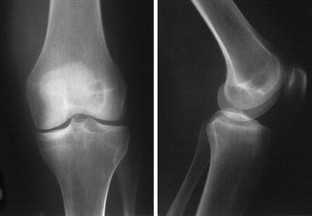

The diagnosis of Charcot arthropathy in the knee is rare. However, there is an increasing number of diabetic patients, and they are living longer due to improvements in treatment. Because neuropathic arthropathy is a late effect of peripheral neuropathy, we can expect an increasing incidence of neuropathic arthropathy. Total knee arthroplasty is the preferred choice of treatment by patients, although it may also be associated with a high incidence of serious complications. This case report presents a young female with diabetes mellitus and Charcot arthropathy of the knee managed by total knee arthroplasty and a literature review. The report encompasses a 5-year follow-up of the patient, from the first contact after knee distortion through diagnosis of Charcot arthropathy and the performance of total knee arthroplasty with outpatient controls. The diagnosis was established on the basis of the rapid destruction of the medial tibial condyle after knee distortion in a patient with neuropathy. Neuropathic arthropathy was confirmed by histology. The patient refused knee fusion and total knee arthroplasty was performed. The patient quickly achieved a painless, stable knee with a 130-degree range of motion. However, a radiolucent line appeared under the tibial component due to premature weight-bearing. The patient was ordered to refrain from weight-bearing for the next 3 months, and the knee was healed. While the management of Charcot arthropathy in the knee remains controversial, total knee arthroplasty is not a contraindication. Early diagnosis, appropriate choice of implant and operative technique, and long-term weight protection are essential.

Fig. 3